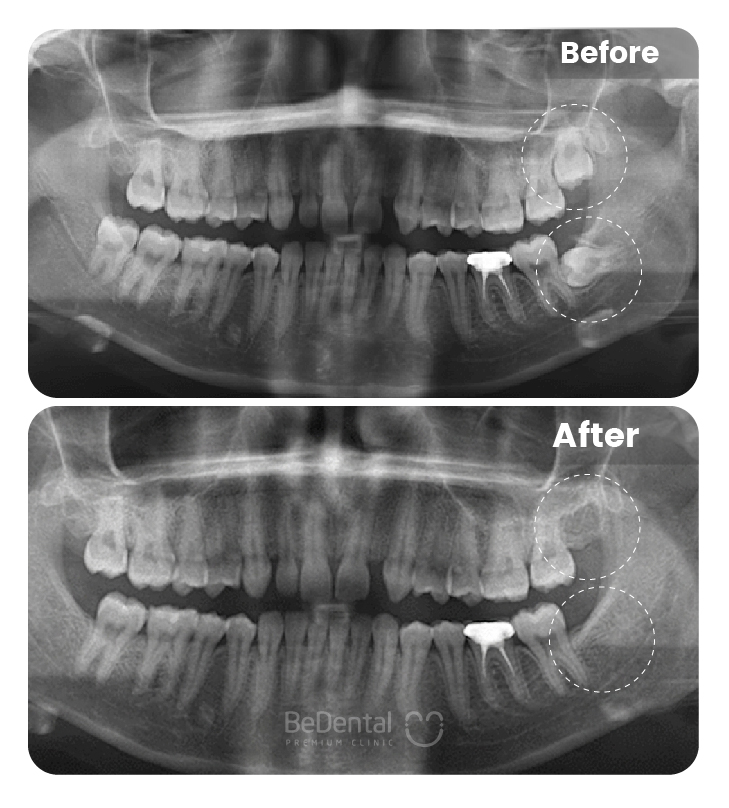

Nhổ răng khôn là thủ thuật nha khoa nhằm loại bỏ răng số 8 mọc lệch, mọc ngầm hoặc gây đau nhức, viêm nhiễm. Với sự hỗ trợ của công nghệ hiện đại và gây tê an toàn, quá trình nhổ răng diễn ra nhanh chóng, hạn chế đau, giúp ngăn ngừa biến chứng và bảo vệ sức khỏe răng miệng lâu dài.